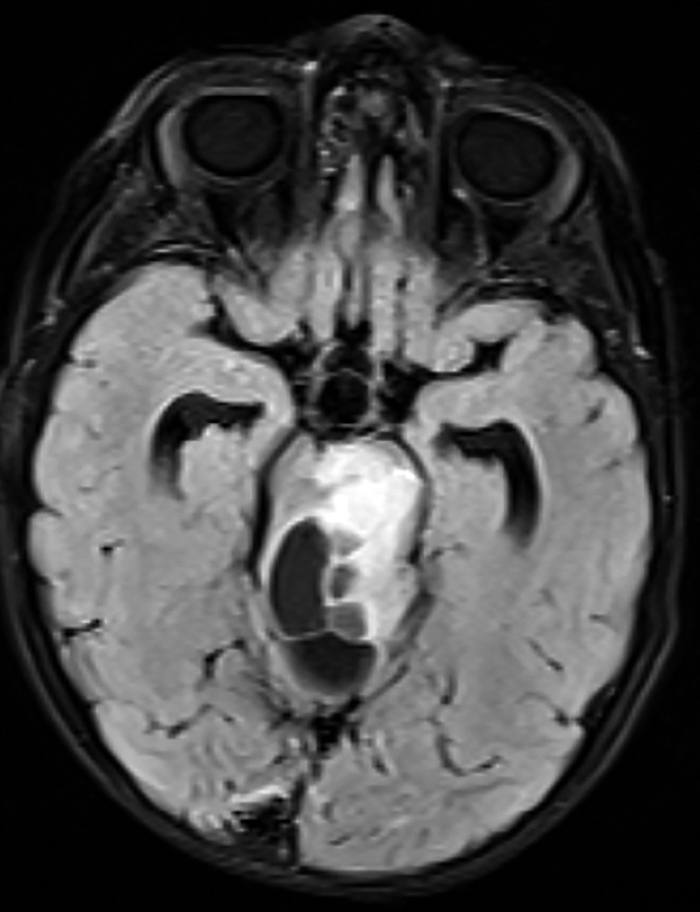

Pacientul I.T., în vârstă de 2 ani și 7 luni, fără antecedente heredocolaterale sau personale semnificative, s-a internat pentru asimetrie facială remarcată de la naștere, asociată cu laterocolis drept. Anterior cu o lună față de internarea curentă a fost evaluat neurologic, fiind observat un frust deficit la nivelul hemicorpului drept. La internare, examenul clinic a fost normal. Examenul neurologic a evidențiat pareză facială dreaptă de tip central și frustă hemipareză dreaptă. S-a efectuat IRM cerebral cu substanță de contrast, ce a evidențiat o formațiune tumorală, posibil astrocitompilocitic la nivelul trunchiului cerebral (figurile 1 și 2).

Figura 2. IRM cerebral secvență T1 ponderată, secțiune transversală, formațiune tumorală la nivelul trunchiului cerebral (imagine din arhiva secției de Neurologie Pediatrică a Spitalului de Copii „Dr. Victor Gomoiu” București)